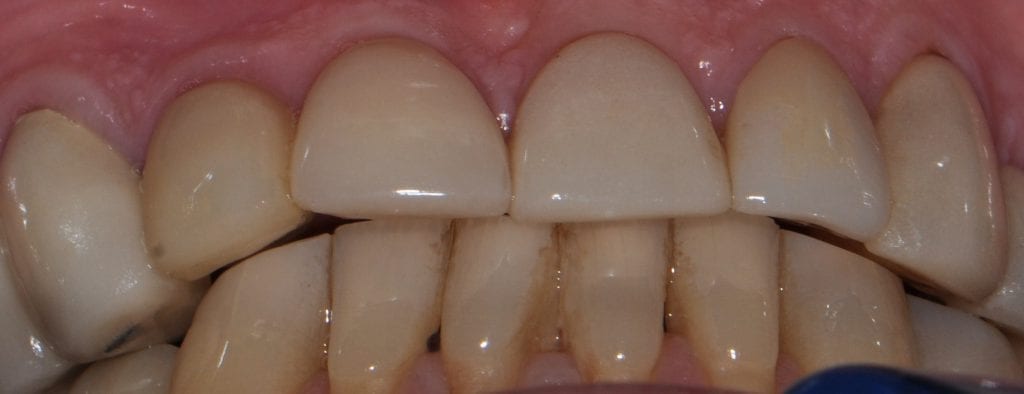

Pre-existing restorations that warranted replacement with an increase in vertical dimension.

Pre-existing restorations that warranted replacement with an increase in vertical dimension. The upper and lower arch were captured with the medit I500 and articulated together with enough clearance to accommodate new restorations and to restore the patient to an ideal tooth position.